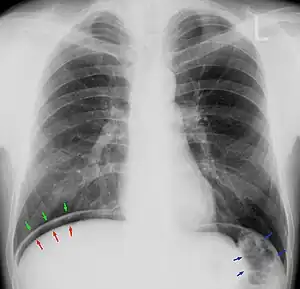

![]() | |

| Chest X-ray with air between the right diaphragm and the liver (green and red arrows). Air also visible below the diaphragm on the persons left. Blue arrows mark a normal gas filled colon. | |